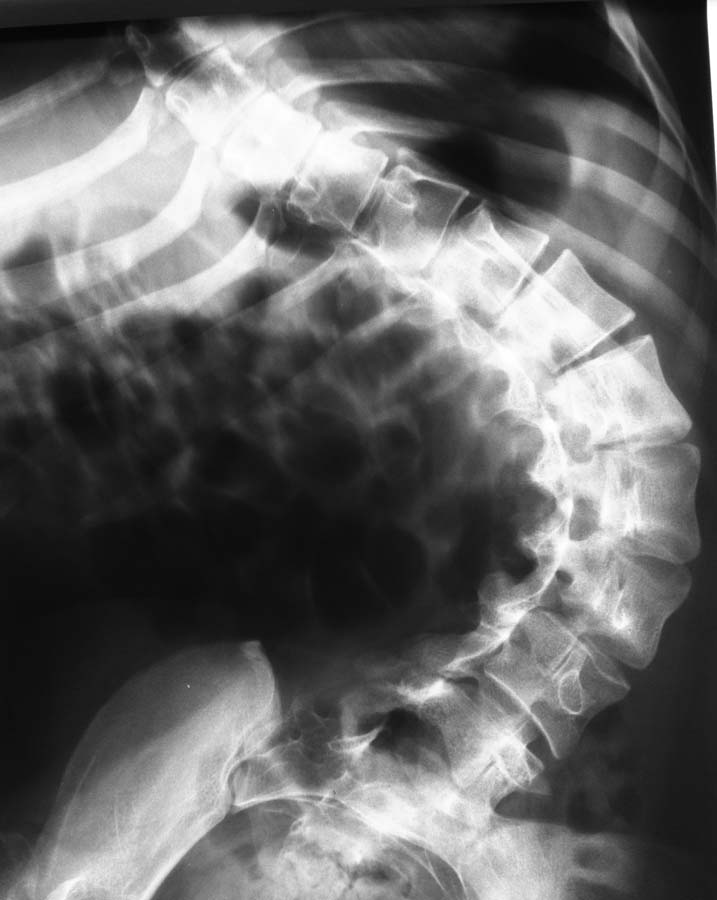

Пациентка 1992 г.р. Болеет ДЦП с рождения. до 2005 г. наблюдалась у неврологов , ходила с

поддержкой. В 2005 г. перелом средней трети бедра. Лечилась консервативно в больнице

Краснодара.

После лечения постепенно стала наростать укорочение конечности и искривление

позвоночника. На представленных Р-гр состояние на сегодняшний день. больная занимает

вынужденное полулежачее состояние. Вопрос где нибудь на просторах РФ могут помочь?????